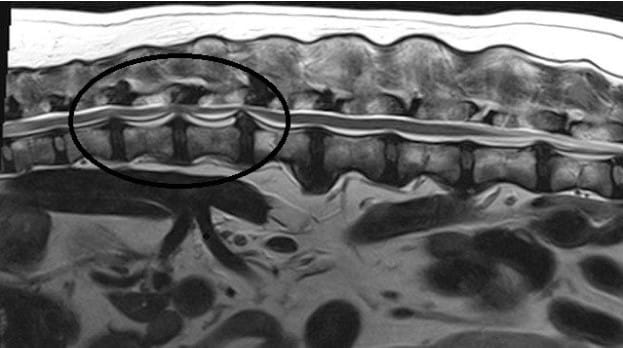

How Herniated Disc Disease Is Diagnosed

Diagnostic Steps

- Full neurologic examination

- Advanced imaging: MRI (gold standard), CT scan (selected cases)

X-rays alone cannot confirm a disc herniation.